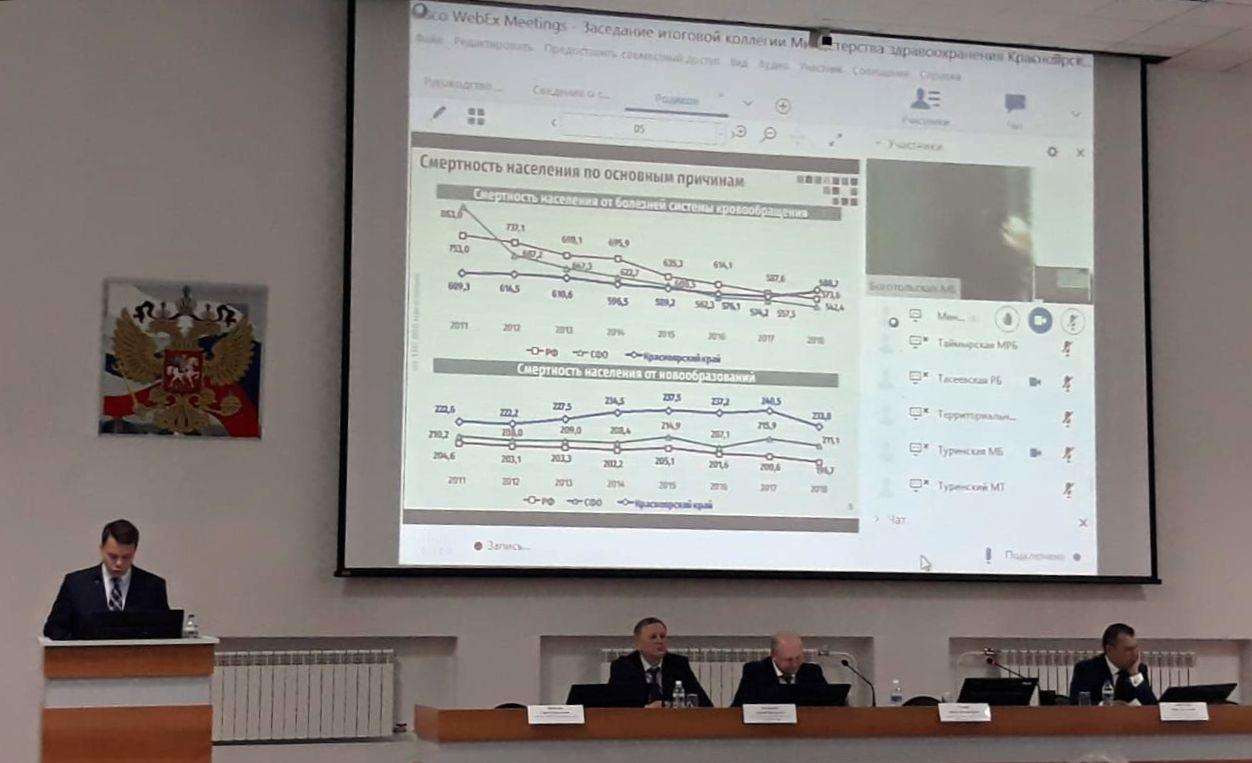

21.03.2022

Состоялась итоговая коллегия Министерства здравоохранения Красноярского края

Участие в заседании коллегии министерства здравоохранения Красноярского края

Подробнее...